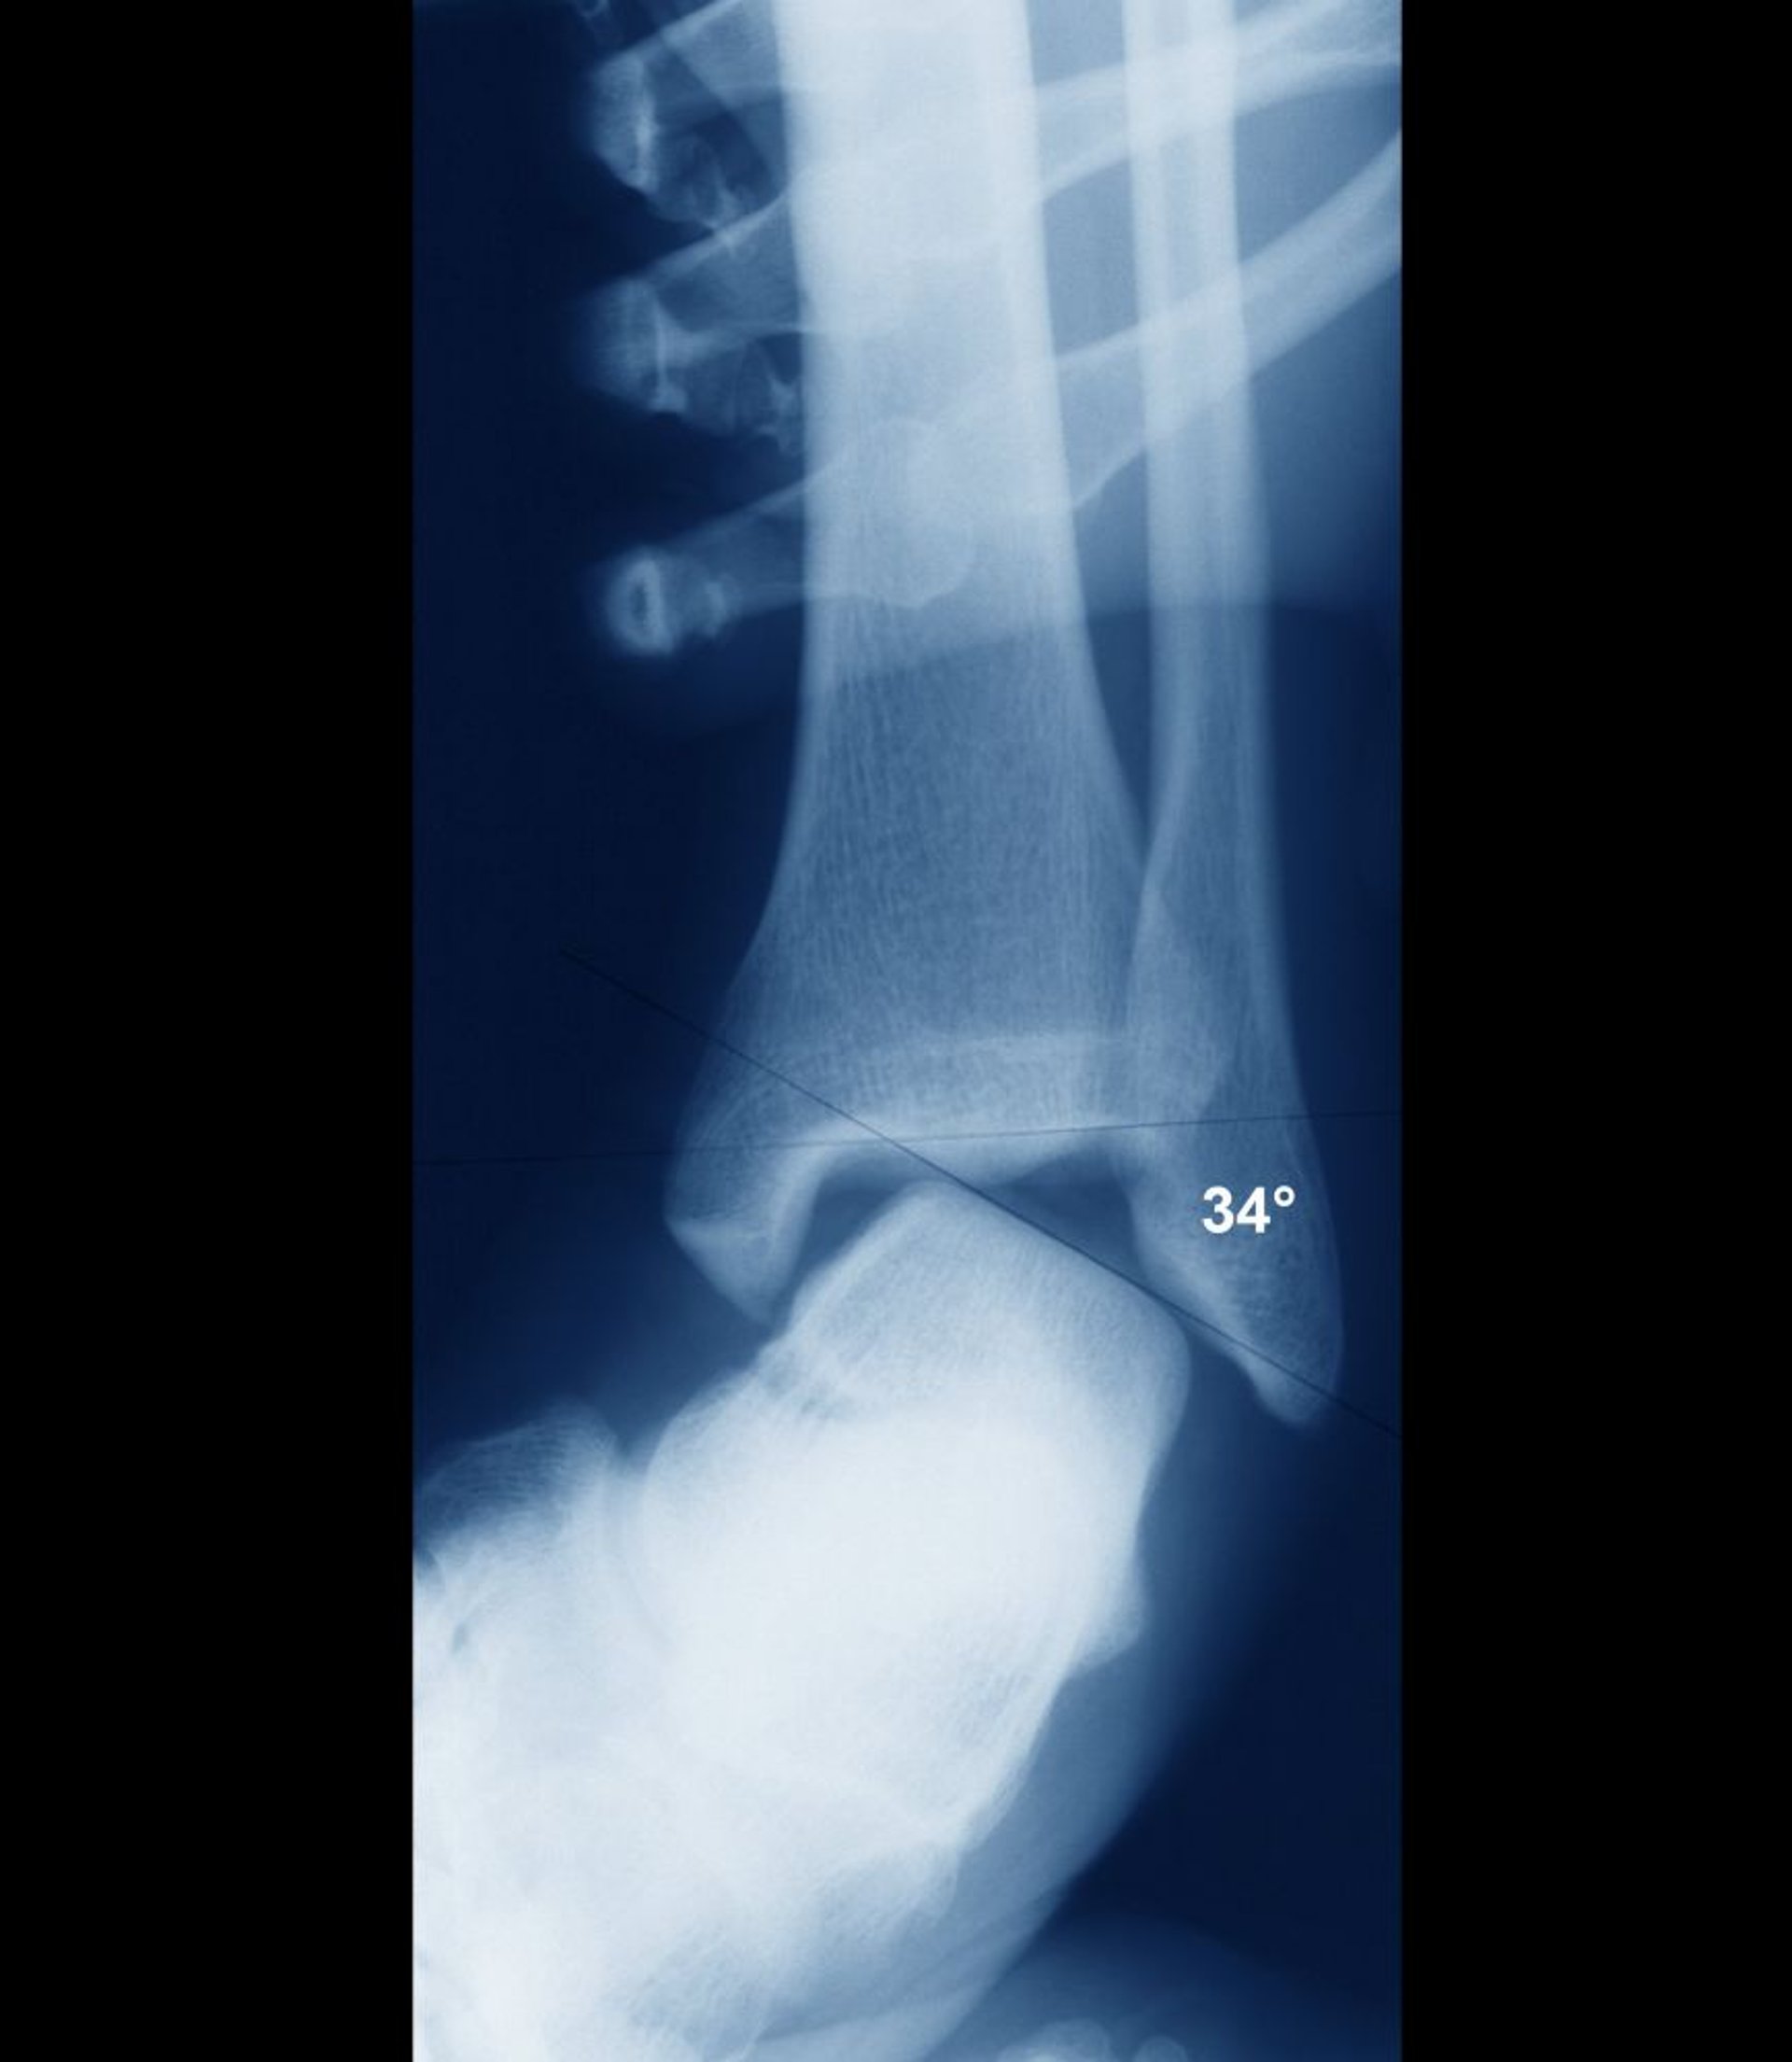

Verstauchung des Sprunggelenks mit Instabilität

Wenn das Sprunggelenk stabil ist, sollten die intraartikulären Oberflächen von Talus und Tibia parallel verlaufen. Hier sind sie weitgehend falsch ausgerichtet, was auf eine grobe Gelenkinstabilität hinweist. Die Instabilität wäre klinisch klar erkennbar gewesen, und die Instabilität wird normalerweise klinisch beurteilt, ohne dass Röntgenaufnahmen erforderlich sind.

ZEPHYR/SCIENCE PHOTO LIBRARY